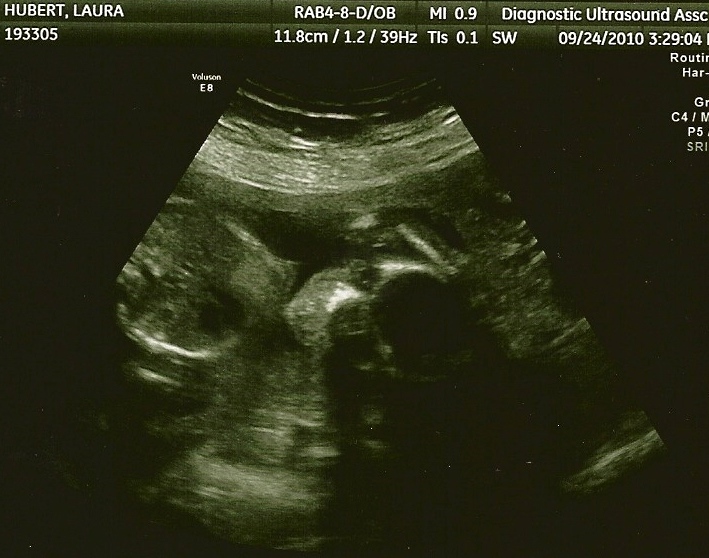

Ultrasound Pictures

18 weeks

9/24/10